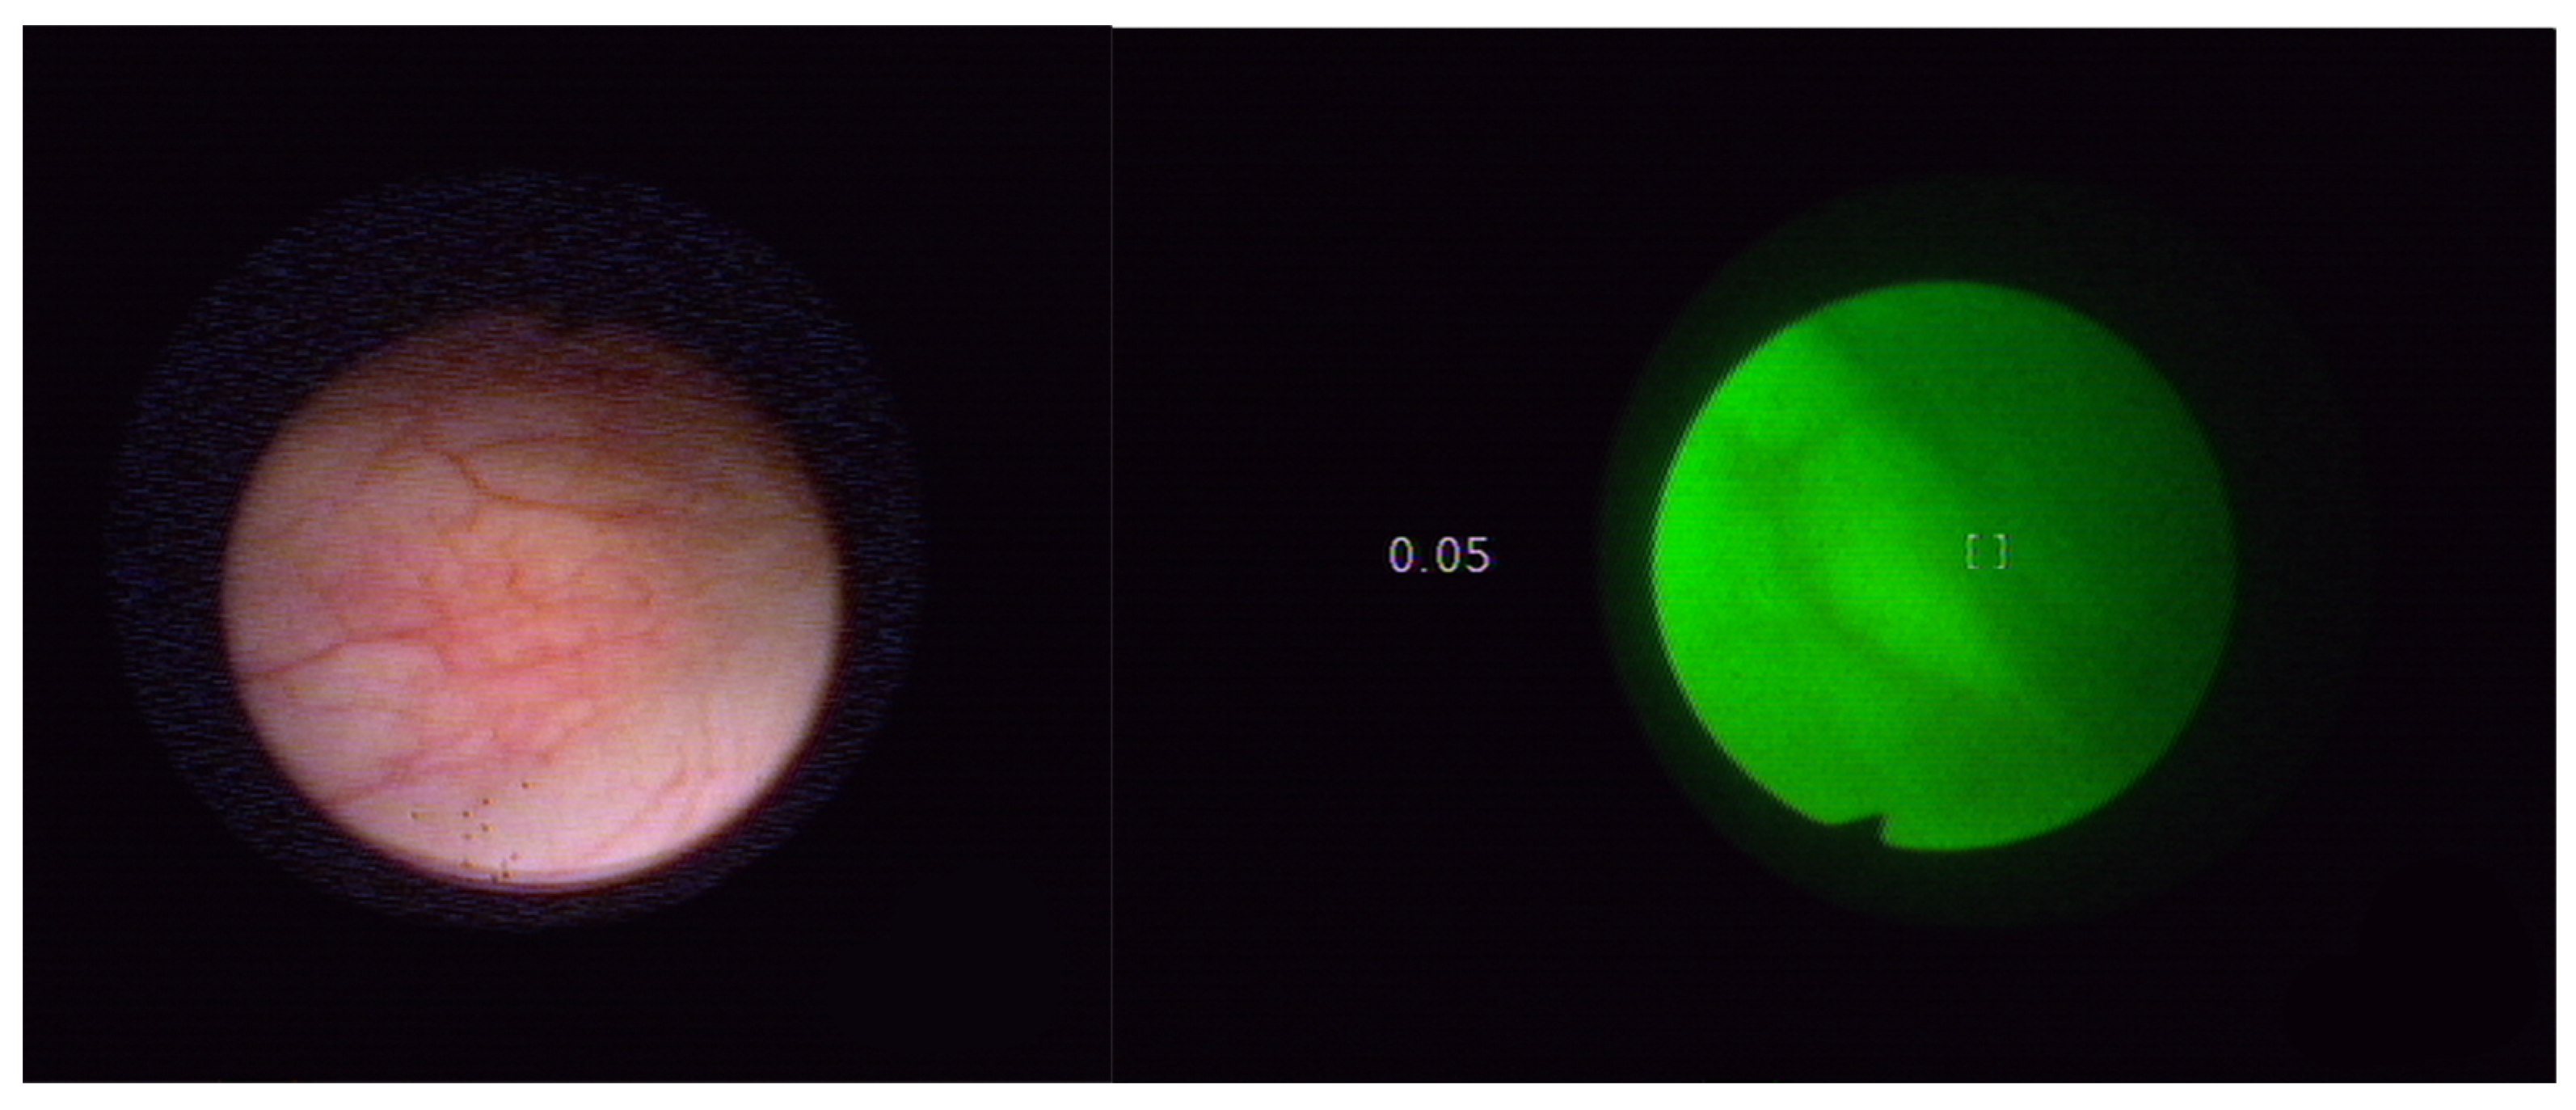

- Szygula, M.; Wojciechowski, B.; Adamek, M.; Pietrusa, A.; Kawczyk-Krupka, A.; Cebula, W.; Zieleznik, W.; Biniszkiewicz, T.; Duda, W.; Sieroń, A. Fluorescent diagnosis of urinary bladder cancer-a comparison of two diagnostic modalities. Photodiagnosis Photodyn. Ther. 2004, 1, 23–26. [Google Scholar] [CrossRef]

- Sim, H.G.; Lau, W.K.; Olivo, M.; Tan, P.H.; Cheng, C.W. Is photodynamic diagnosis using hypericin better than white-light cystoscopy for detecting superficial bladder carcinoma? BJU Int. 2005, 95, 1215–1218. [Google Scholar] [CrossRef] [PubMed]